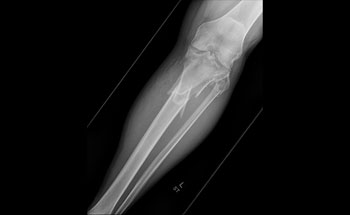

Acute-Compartment-Syndrome-2-Coe-Web-Ready.jpg

Photo Courtesy of Marcus P. Coe, MD, MS, FAOA, FAAOS